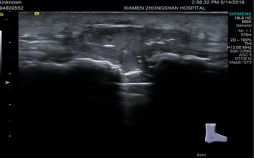

肌骨超声用于康复治疗

肌骨超声用于风湿病检查